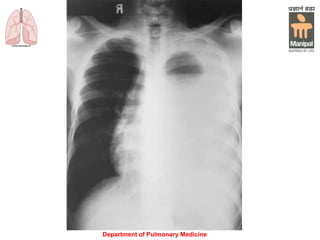

Computed tomography: Bilateral pleural effusions

are present as a result of pneumonia